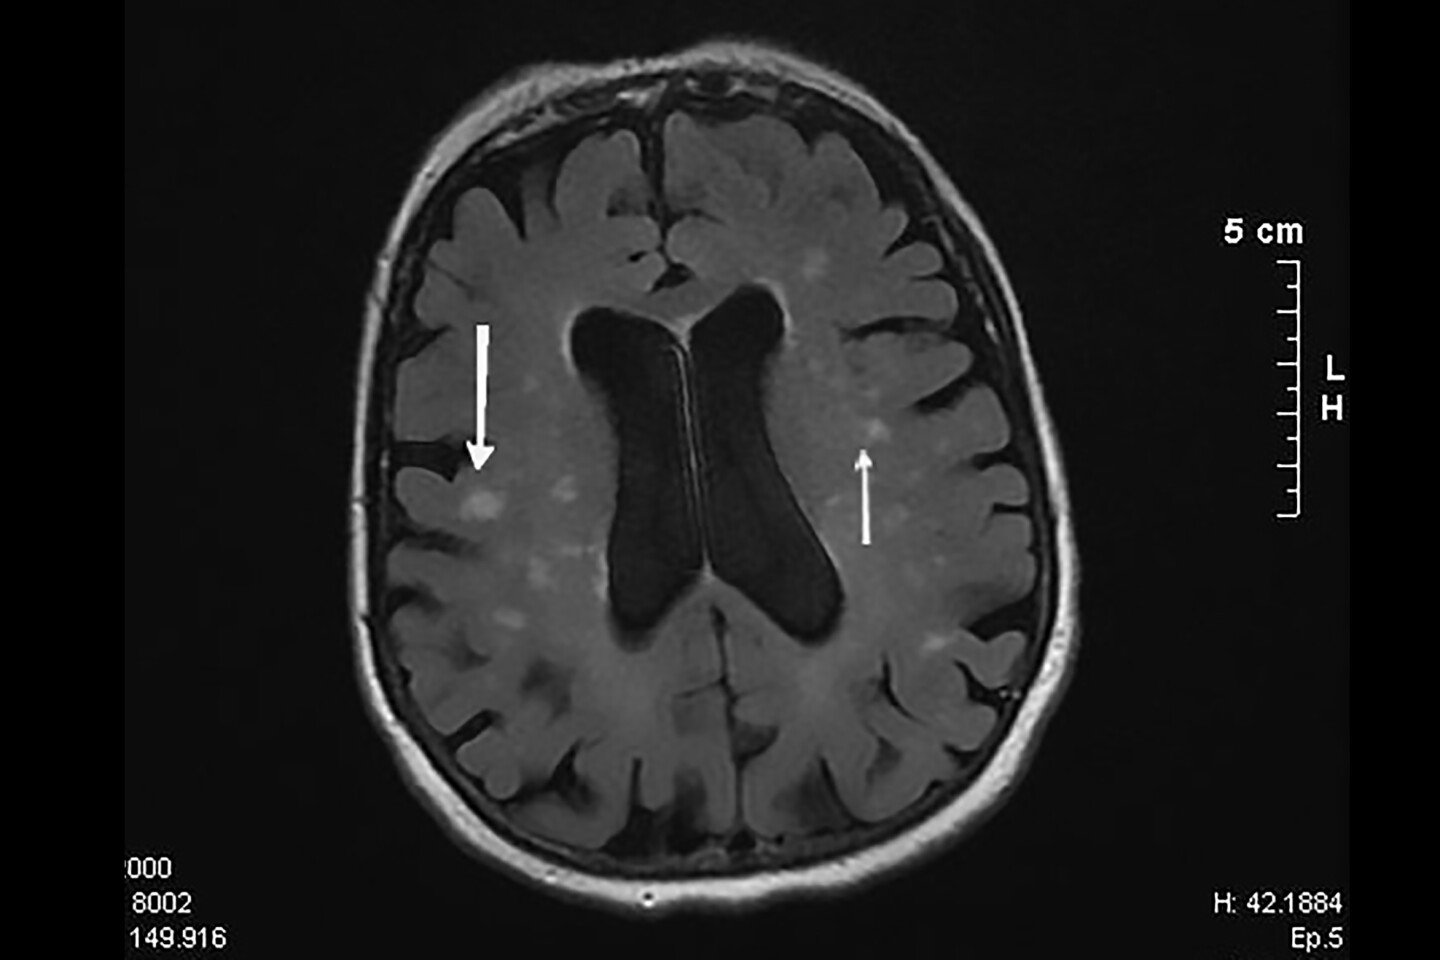

Araştırmacılar, B12 konsantrasyonlarının bilişsel performans ve miyelin bütünlüğü ile ilişkisini değerlendirdiler. Miyelin, sinir liflerinin etrafındaki koruyucu kaplamadır ve düzgün sinir fonksiyonu için çok önemlidir. B12 vitamini, bunu korumada önemli bir rol oynar. B12 eksik olduğunda, vücut miyelin bütünlüğünü onarmak ve korumak için mücadele eder. Beyin dokusunun sağlığını değerlendirmek için manyetik rezonans görüntüleme (MRI) taramaları yapıldı.

Düşük Holo-TC ayrıca görme ile ilgili daha yavaş sinir sinyallemesiyle de bağlantılıydı. Ek olarak, MRI taramaları, daha düşük Holo-TC’ye sahip katılımcıların daha fazla ‘beyaz cevher hiperintensitesi’ (WMH) olduğunu, yaşlanma, zayıf dolaşım veya felç veya bunama gibi nörolojik hastalıklarla ilişkili beynin beyaz cevherindeki küçük hasar alanları olduğunu ortaya koydu. Araştırmacılar, bu çalışmadan MRI’da görülen WMH’nin doğrudan düşük B12’nin bir sonucu olup olmadığını söyleyemediler.